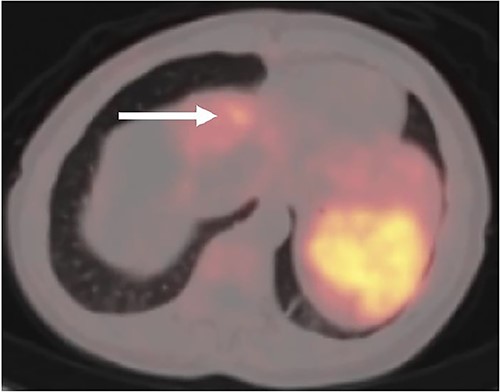

A (68Ga) DOTATATE PET/CT was performed 1 month postoperatively for surveillance purposes which revealed a 1 cm intense lesion in segment 4A of the liver, as well as several radiotracer avid osseous foci involving the left parietal bone, T9 and L1 vertebrae, and left proximal humerus, concerning for further metastatic disease (Fig. 3). The patient was discussed at a multidisciplinary tumor board, and the decision was for ongoing surveillance to her liver with the option for liver directed therapy should the segment 4A lesion grow as well as to proceed with radiation treatment to the vertebral lesions.

Postoperative (68Ga) DOTATATE PET/CT imaging demonstrating 1 cm intense lesion in segment 4A of the left hemiliver (white arrow).